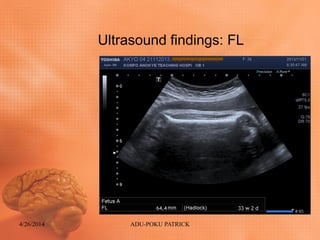

Ultrasound findings: FL

GA from Fetal Biometry

• The fetal biometry showed significant

growth inconsistencies

• BPD-More than 41weeks

• HC -39weeks

• AC- 35weeks

• FL- 33weeks 2days

TABLE